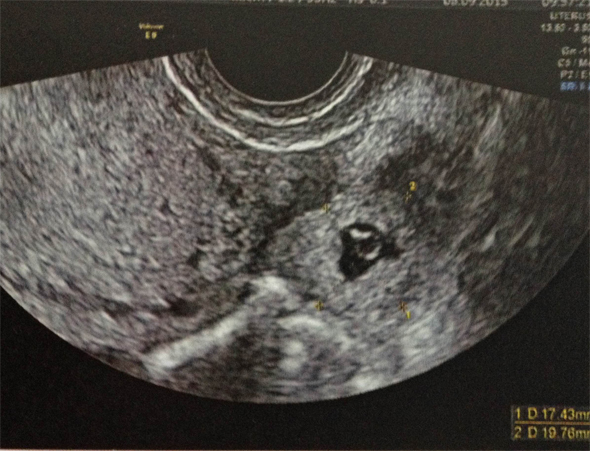

On évoque, en priorité les diagnostics d’urgence ( = diagnostics GRAVES ), donc GEU , la salpingite et la torsion d’annexe.

La GEU en priorité

Rappel : TOUTE FEMME EN AGE DE PROCREER PRESENTANT DES METRORRAGIES ET/OU DES DOULEURS PELVIENNES A UNE GEU JUSQU'A PREUVE DU CONTRAIRE